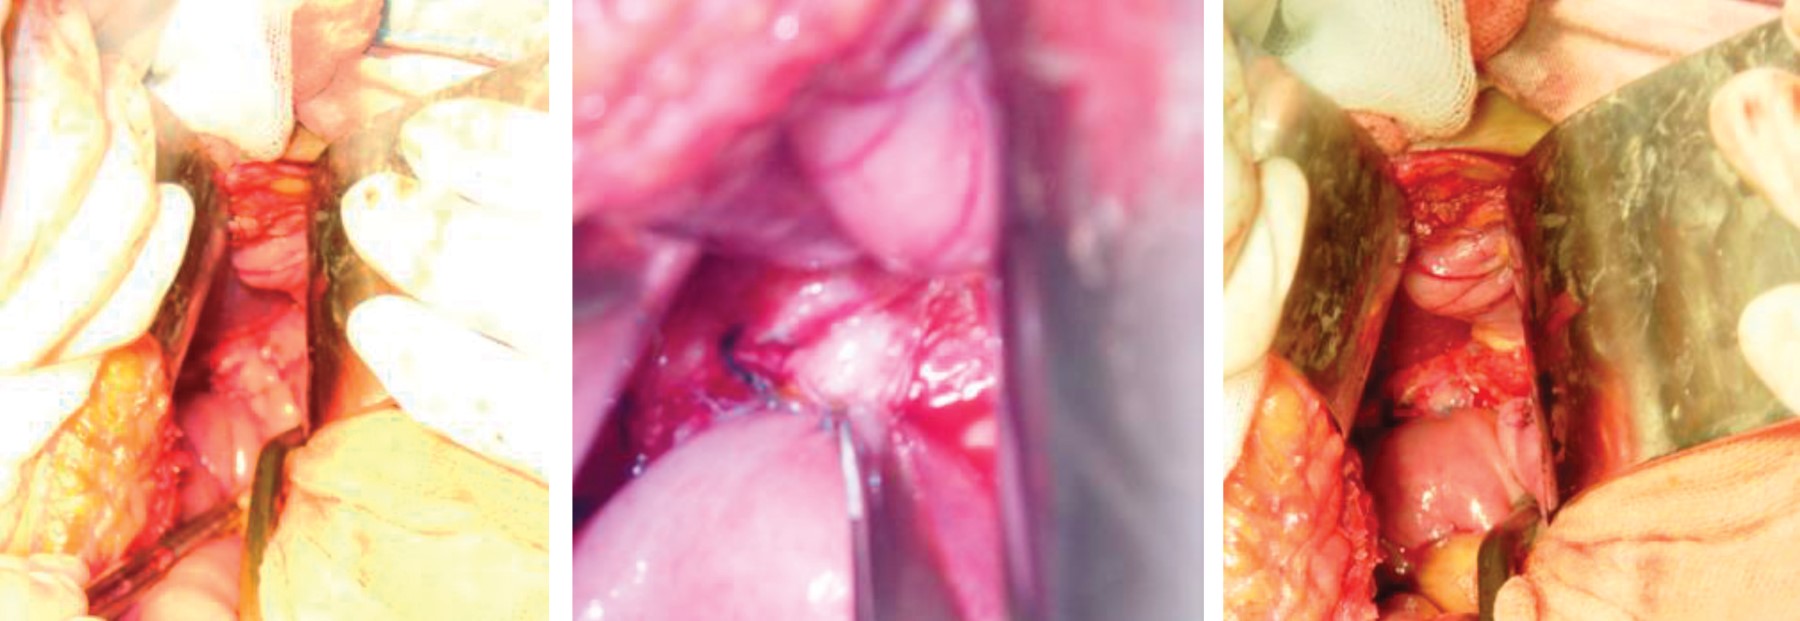

Under mixed anesthetic block, after asepsis and antisepsis of the region, sterile fields were placed and a right subcostal incision was made. The dissection was performed by planes until reaching the abdominal cavity. The gallbladder was identified, and dissection of the cystic and its artery was started. Then the gallbladder was dissected in an anterograde way until reaching its union with the common bile duct; the common bile duct was dissected along the cyst. The bleeding vessels were clamped, cut and ligated with 2-0 silk suture, then the proximal portion of the common bile duct was sectioned and dissected until reaching its distal portion, which was clamped, cut and ligated. Then the jejunum was sectioned approximately 40 cm from the Treitz ligament, and an end-to-side anastomosis was performed in two planes with a 3-0 Vicryl and a 2-0 silk sutures at 70 cm from the loop that goes towards the common hepatic duct. Then, a hepato-jejunal anastomosis was performed with 3-0 prolene sutures in one plane (Figure 5).

Operative findings: a common bile duct cyst of approximately 6 × 4 cm, gallbladder without stones was found, and the liver was of normal appearance (Figures 6 and 7).